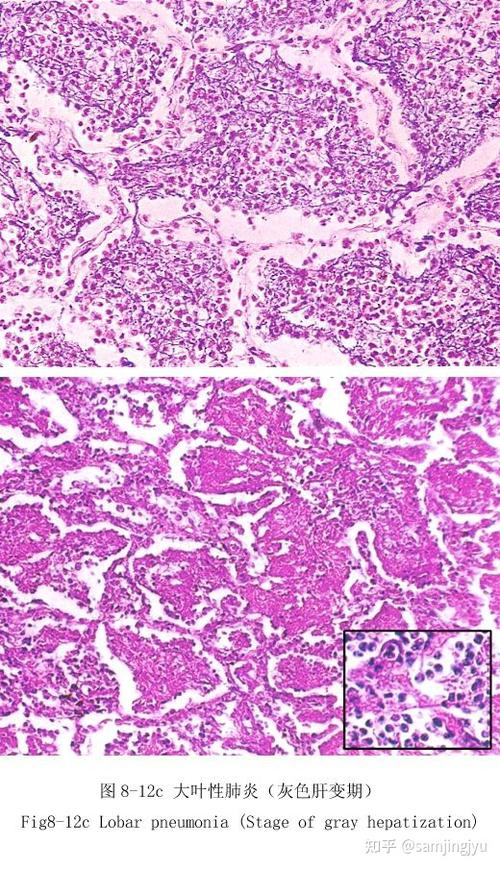

大叶性肺炎切片

大叶性肺炎切片,慢性肺瘀血

大叶性肺炎

大叶性肺炎小叶性肺炎病理组织切片

7.大叶性肺炎

大叶性肺炎灰肝期绘图